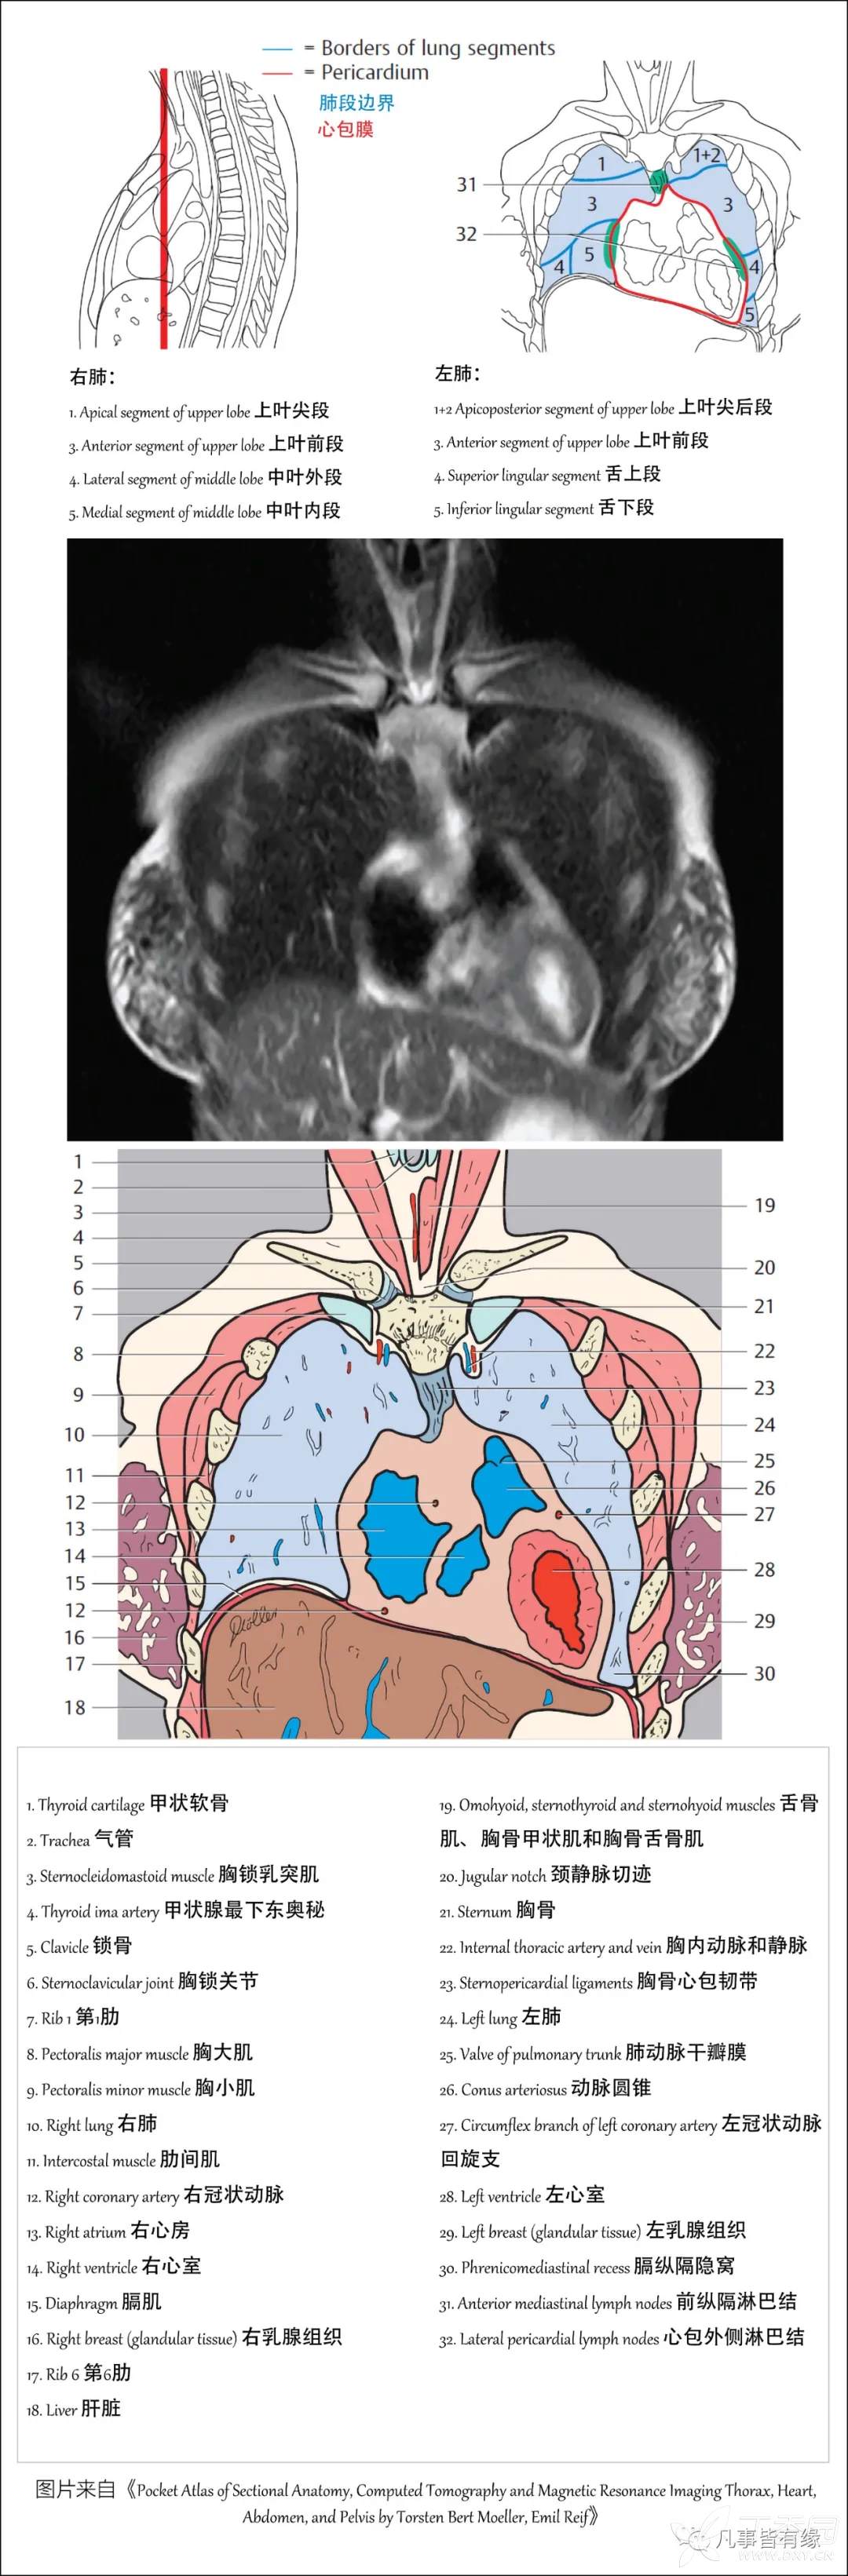

(一)胸部CT轴位断层解剖: